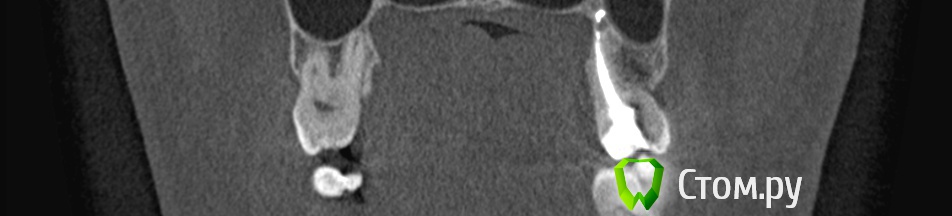

winnt Опубликовано 18 июля, 2014 Автор Поделиться Опубликовано 18 июля, 2014 Еще добавлю срез КТ, между 7 и 8 : Ссылка на комментарий

winnt Опубликовано 18 июля, 2014 Автор Поделиться Опубликовано 18 июля, 2014 То есть 7ой зуб чувствует холод? Болит меньше когда прикладываете? А скололся скорее всего из-за кариеса, антогонист скол не вызовет, либо стираемость может быть и увеличение чувствительности. Пломбу вам случаем не завысили?Холод чувствует, но как-то тупее чем здоровый зуб и боль остается дольше после холодного;Когда прикладываю болит больше и после того как убираю боль "остается" дольше чем в здоровом;Скололся от удара нижней челюстью об торпеду авто;Пломбу не завысили, это точно. Покрутил в КТ этот зуб и стало чуть страшно будто от корня этого зуба "что-то растет" прямо в НЧ.канал: Ссылка на комментарий

Гарриевич Опубликовано 18 июля, 2014 Поделиться Опубликовано 18 июля, 2014 на последнем снимке остеит, то есть хронические периапикальные изменения есть. скорее всего травма вызвала ответную реакцию пульпы зуба и ее частичное поражение. желательна конечно очная консультация 1 Ссылка на комментарий